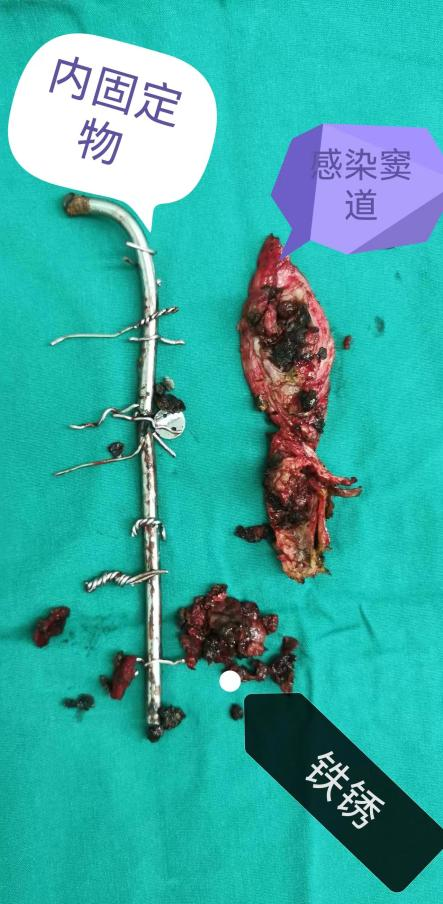

体位摆好,顺利消毒铺巾后,医生开刀后,发现陈伯背上形成一条长长的窦道,里面填满了黄色的脓液,而里面的内固定物已经被腐蚀断裂,锈迹斑斑了。

图源:骨一科

手术中

窦道与脓液

陈伯的情况较为特殊,其30多年前使用的内固定材料为不锈钢,与人体的生物相容性欠佳,而且术后感染了,形成窦道,造成内固定物腐蚀断裂、感染无法控制,故需要拆除内固定。